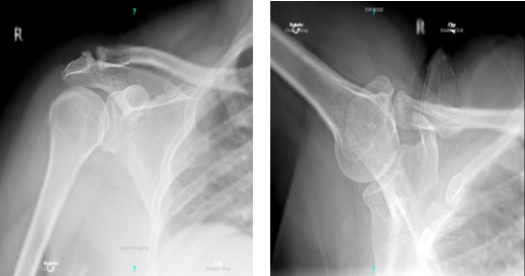

The patient is a 54-year-old female who came into the office after falling and being unable to move her shoulder. She was in a lot of discomfort. The examination revealed a rotator cuff tear. An MRI revealed a significant rotator cuff tear in the left shoulder as well as a biceps subluxation.

X-ray bilateral shoulders